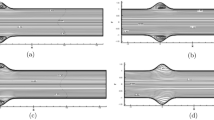

Surgical planning as a treatment for vascular diseases requires fast blood flow simulations that are efficient in handling changing geometry. It is, for example, necessary to try different paths of a planned by pass and study the resulting hemodynamic flow fields before deciding the final geometrical solution. With the aid of a real time interactive simulation environment that uses an efficient flow solver, this allows flexible treatment planning. In this article, we demonstrate that the lattice Boltzmann method can be an alternative robust CFD technique for such kind of applications. Steady flow in a 2D symmetric bifurcation is studied and the obtained flow fields and stress tensor components are compared to those obtained by a Navier-Stokes (NS) solver. We also demonstrate that the method is fully adaptive to interactively changing geometry.